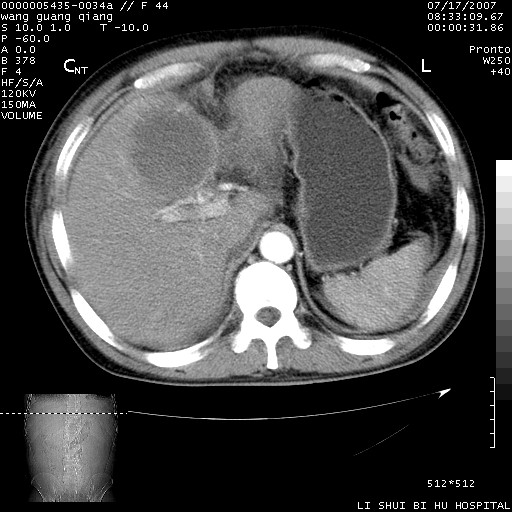

以下是引用dyqct在2007-7-18 10:46:00的发言:[br]胆囊明显增大,壁增厚,明显强化;后下方见大片高密度区,ct值68hu,无强化,周围见多数条纹状高密度影,边界不清。双膈下间隙、肝肾隐窝见带状及片状低密度区。[br]右侧胸壁后缘亦见新月形水样密度区。[br]考虑:1、急性胆囊炎伴周围出血;[br] 2、少量腹水、右侧少量胸腔积液。[br][br][本贴已被 dyqct 于 2007-7-18 10:48:47 修改过]